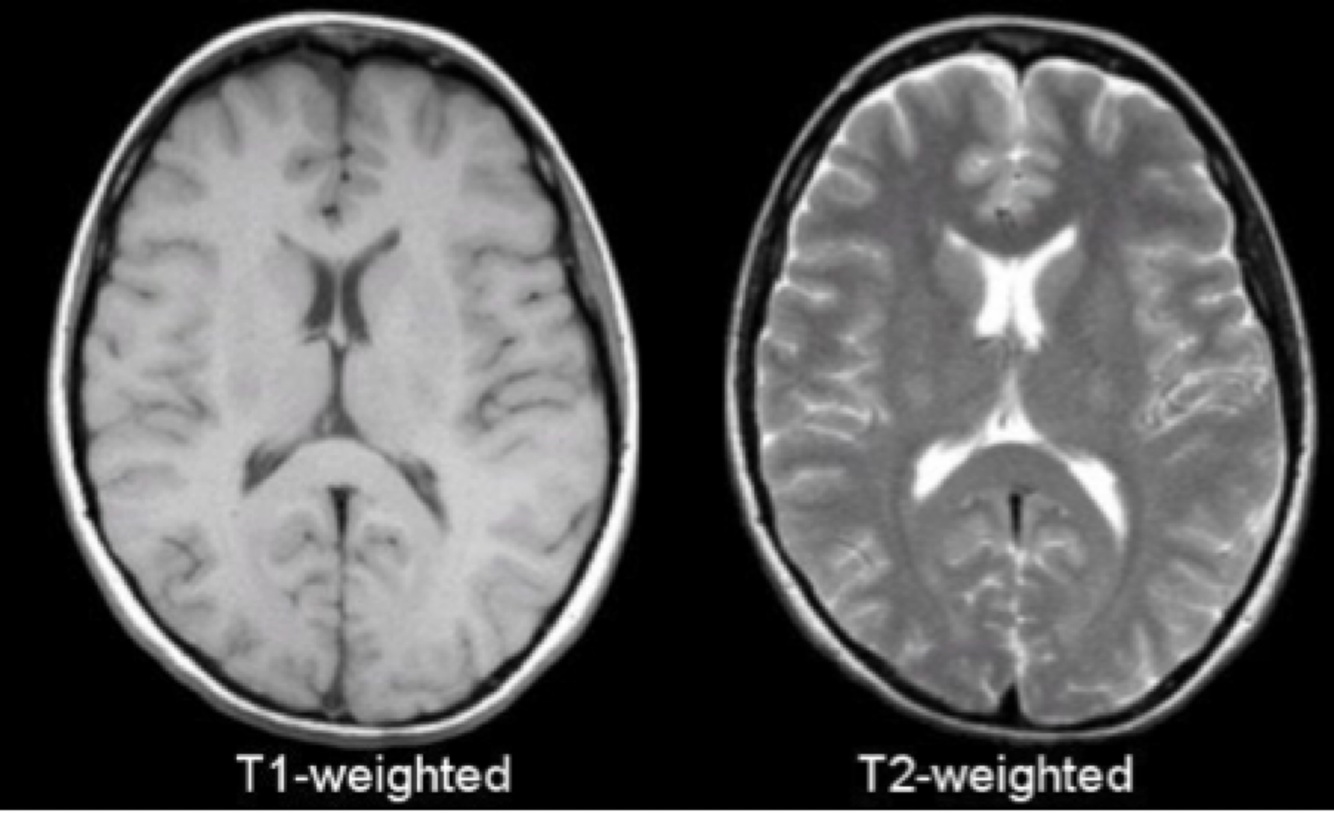

T1 weighted:

An image where the contrast depends predominantly on the differences in the T1 … times between tissues

The TR controls how far each … recovers before the next slice is excited by the next radiofrequency pulse

An image where the contrast depends predominantly on the differences in the T1 RELAXATION times between tissues

The TR controls how far each VECTOR recovers before the next slice is excited by the next radiofrequency pulse

T1 weighted image:

… time (TR) is crucial for T1 contrast

TR controls how far each vector can recover before it is excited by the next … pulse

For T1 weighting, the TR must be … enough so that neither fat nor water have … time to fully return to Bo

If the TR is too long, then both fat and water will fully recover to the … magnetisation

In that case, the difference in T1 contrast can’t be demonstrated in the image

(Short TR = strong T1 weighting

Long TR = low T1 weighting)

REPETITION time (TR) is crucial for T1 contrast

TR controls how far each vector can recover before it is excited by the next RADIOFREQUENCY pulse

For T1 weighting, the TR must be SHORT enough so that neither fat nor water have SUFFICIENT time to fully return to Bo

If the TR is too long, then both fat and water will fully recover to the LONGITUDINAL magnetisation

T2 weighted:

An image where the contrast depends predominantly on the differences in the T2 … times between tissues

The TE controls the amount of T2 decay that occurs before the signal is received

An image where the contrast depends predominantly on the differences in the T2 DECAY times between tissues

T2 weighted image:

… times between tissues (TE) is crucial for T2 weighting

If a short echo time (25ms) is used, the signal differences between tissues are …

T2 relaxation has only just started and there has only been … signal decay at the time of echo collection

The resulting image has … T2 weighting

ECHO times between tissues (TE) is crucial for T2 weighting

If a short echo time (25ms) is used, the signal differences between tissues are SMALL

T2 relaxation has only just started and there has only been LITTLE signal decay at the time of echo collection

The resulting image has LOW T2 weighting